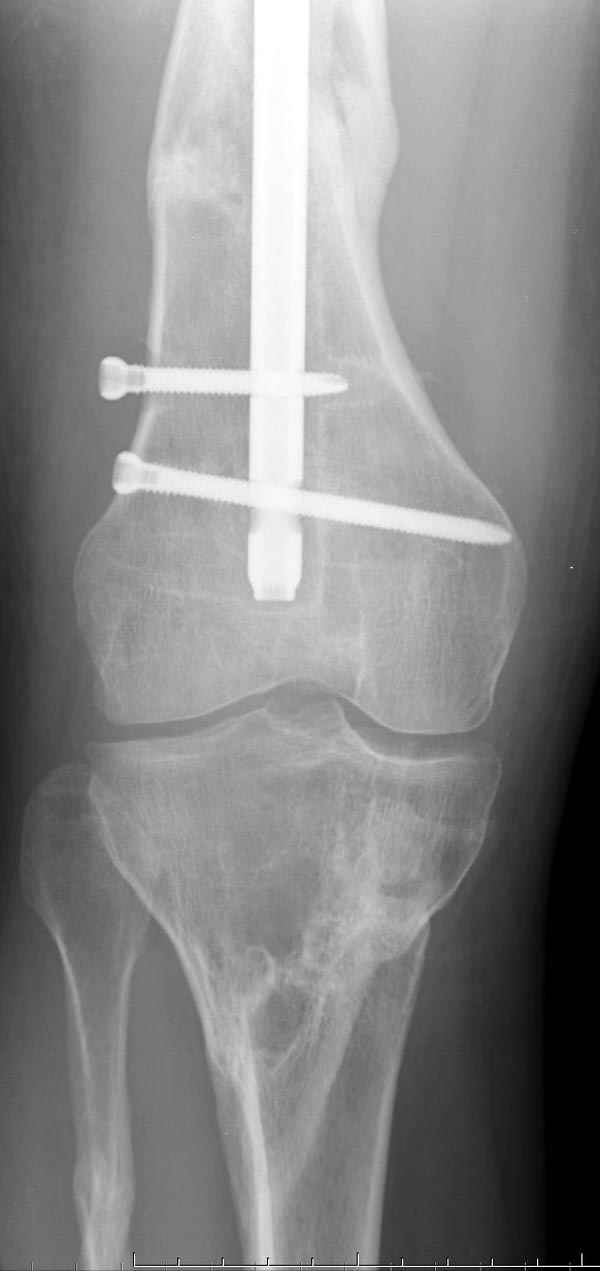

если первые 4 месяца послеоперационного периода проходил без проблем, но на 5 месяце появились боли в дистальном отделе бедра и температура, т.е. симптомы медуллярного инфицирования (рис №3, №4).

Замена реконструктивного штифта “Custom made Nail” с антибиотиком (рис №5, №6),

после промывки канала с рассверливанием внутреннего кортекса, через 4 недели антибиотический штифт удалили, оспалителный процесс остановлен и бедро сросся.

При обзоре причин перелома, на снимке №2 обнаружили, что один из стержней аппарата наружной фиксации проходил только через передний кортекальный слой, что создало стрессовую зону на бедре и в результате перелом из-за незначительной травмы.